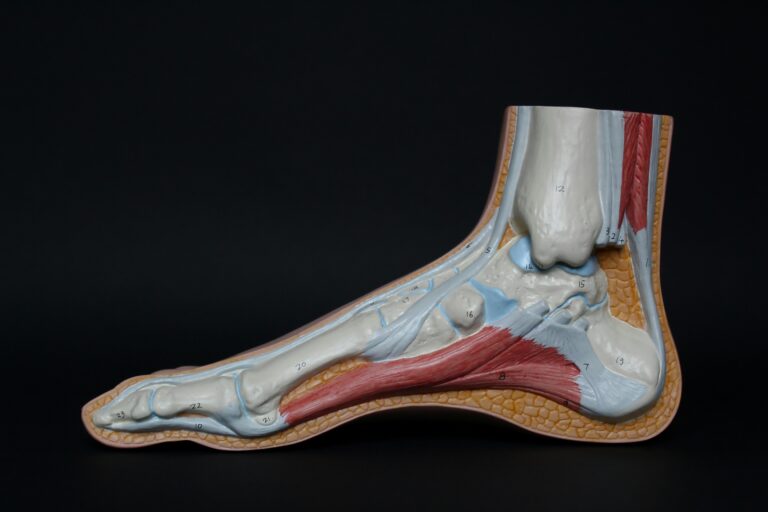

في الالتواء الأول، قد تتمدد الأربطة أو تتمزق. هذه الأربطة هي المسؤولة عن تثبيت الكاحل.

إذا لم تلتئم بشكل كامل، أو لم يستعد الكاحل قوته وتوازنه عبر التأهيل، يبقى المفصل أضعف من الطبيعي.

وهنا تبدأ المشكلة: الكاحل يصبح أكثر عرضة للألم، وأكثر قابلية للالتواء مرة أخرى.

التشخيص يبدأ من القصة المرضية: متى بدأ الألم، كم مرة تكرر الالتواء، هل هناك شعور بعدم الثبات، وهل يزيد الألم مع أرض غير مستوية أو مع النشاط. ثم يأتي الفحص السريري لتقييم موضع الألم، ومدى الحركة، والثبات، والتورم. وإذا وُجد اشتباه في كسر أو إصابة عظمية، قد تُطلب الأشعة السينية. أما إذا كان الهدف تقييم الأربطة أو الأنسجة الرخوة أو البحث عن إصابة لا تظهر بوضوح في الأشعة العادية، فقد يفيد الرنين المغناطيسي.